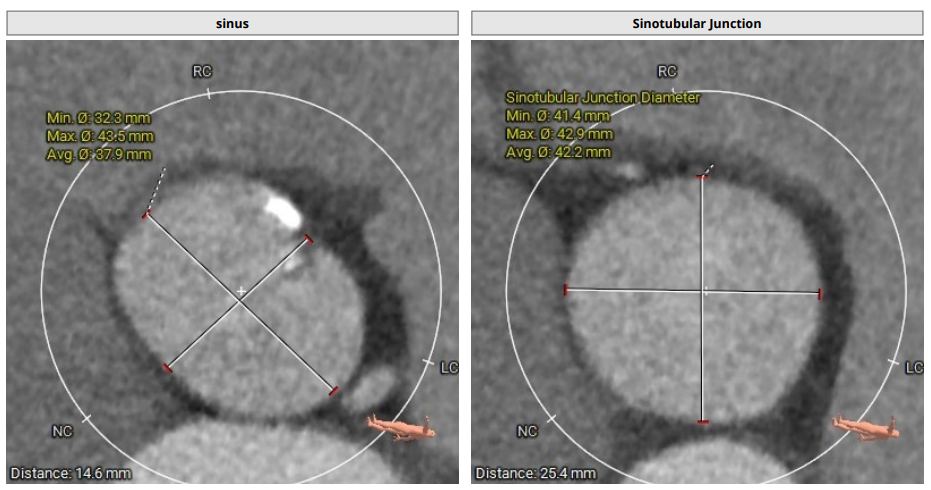

CT分析

TYPE0型二叶瓣,瓣叶增厚,重度钙化,左冠开口高度约18.5mm,右冠开口高度约19mm,法式窦结构大,STJ高度约25.4mm、直径约42.2mm,升主动脉增宽,最宽处约56 mm,心脏角度约60°,左室大。

主动脉根部解剖及入路分析